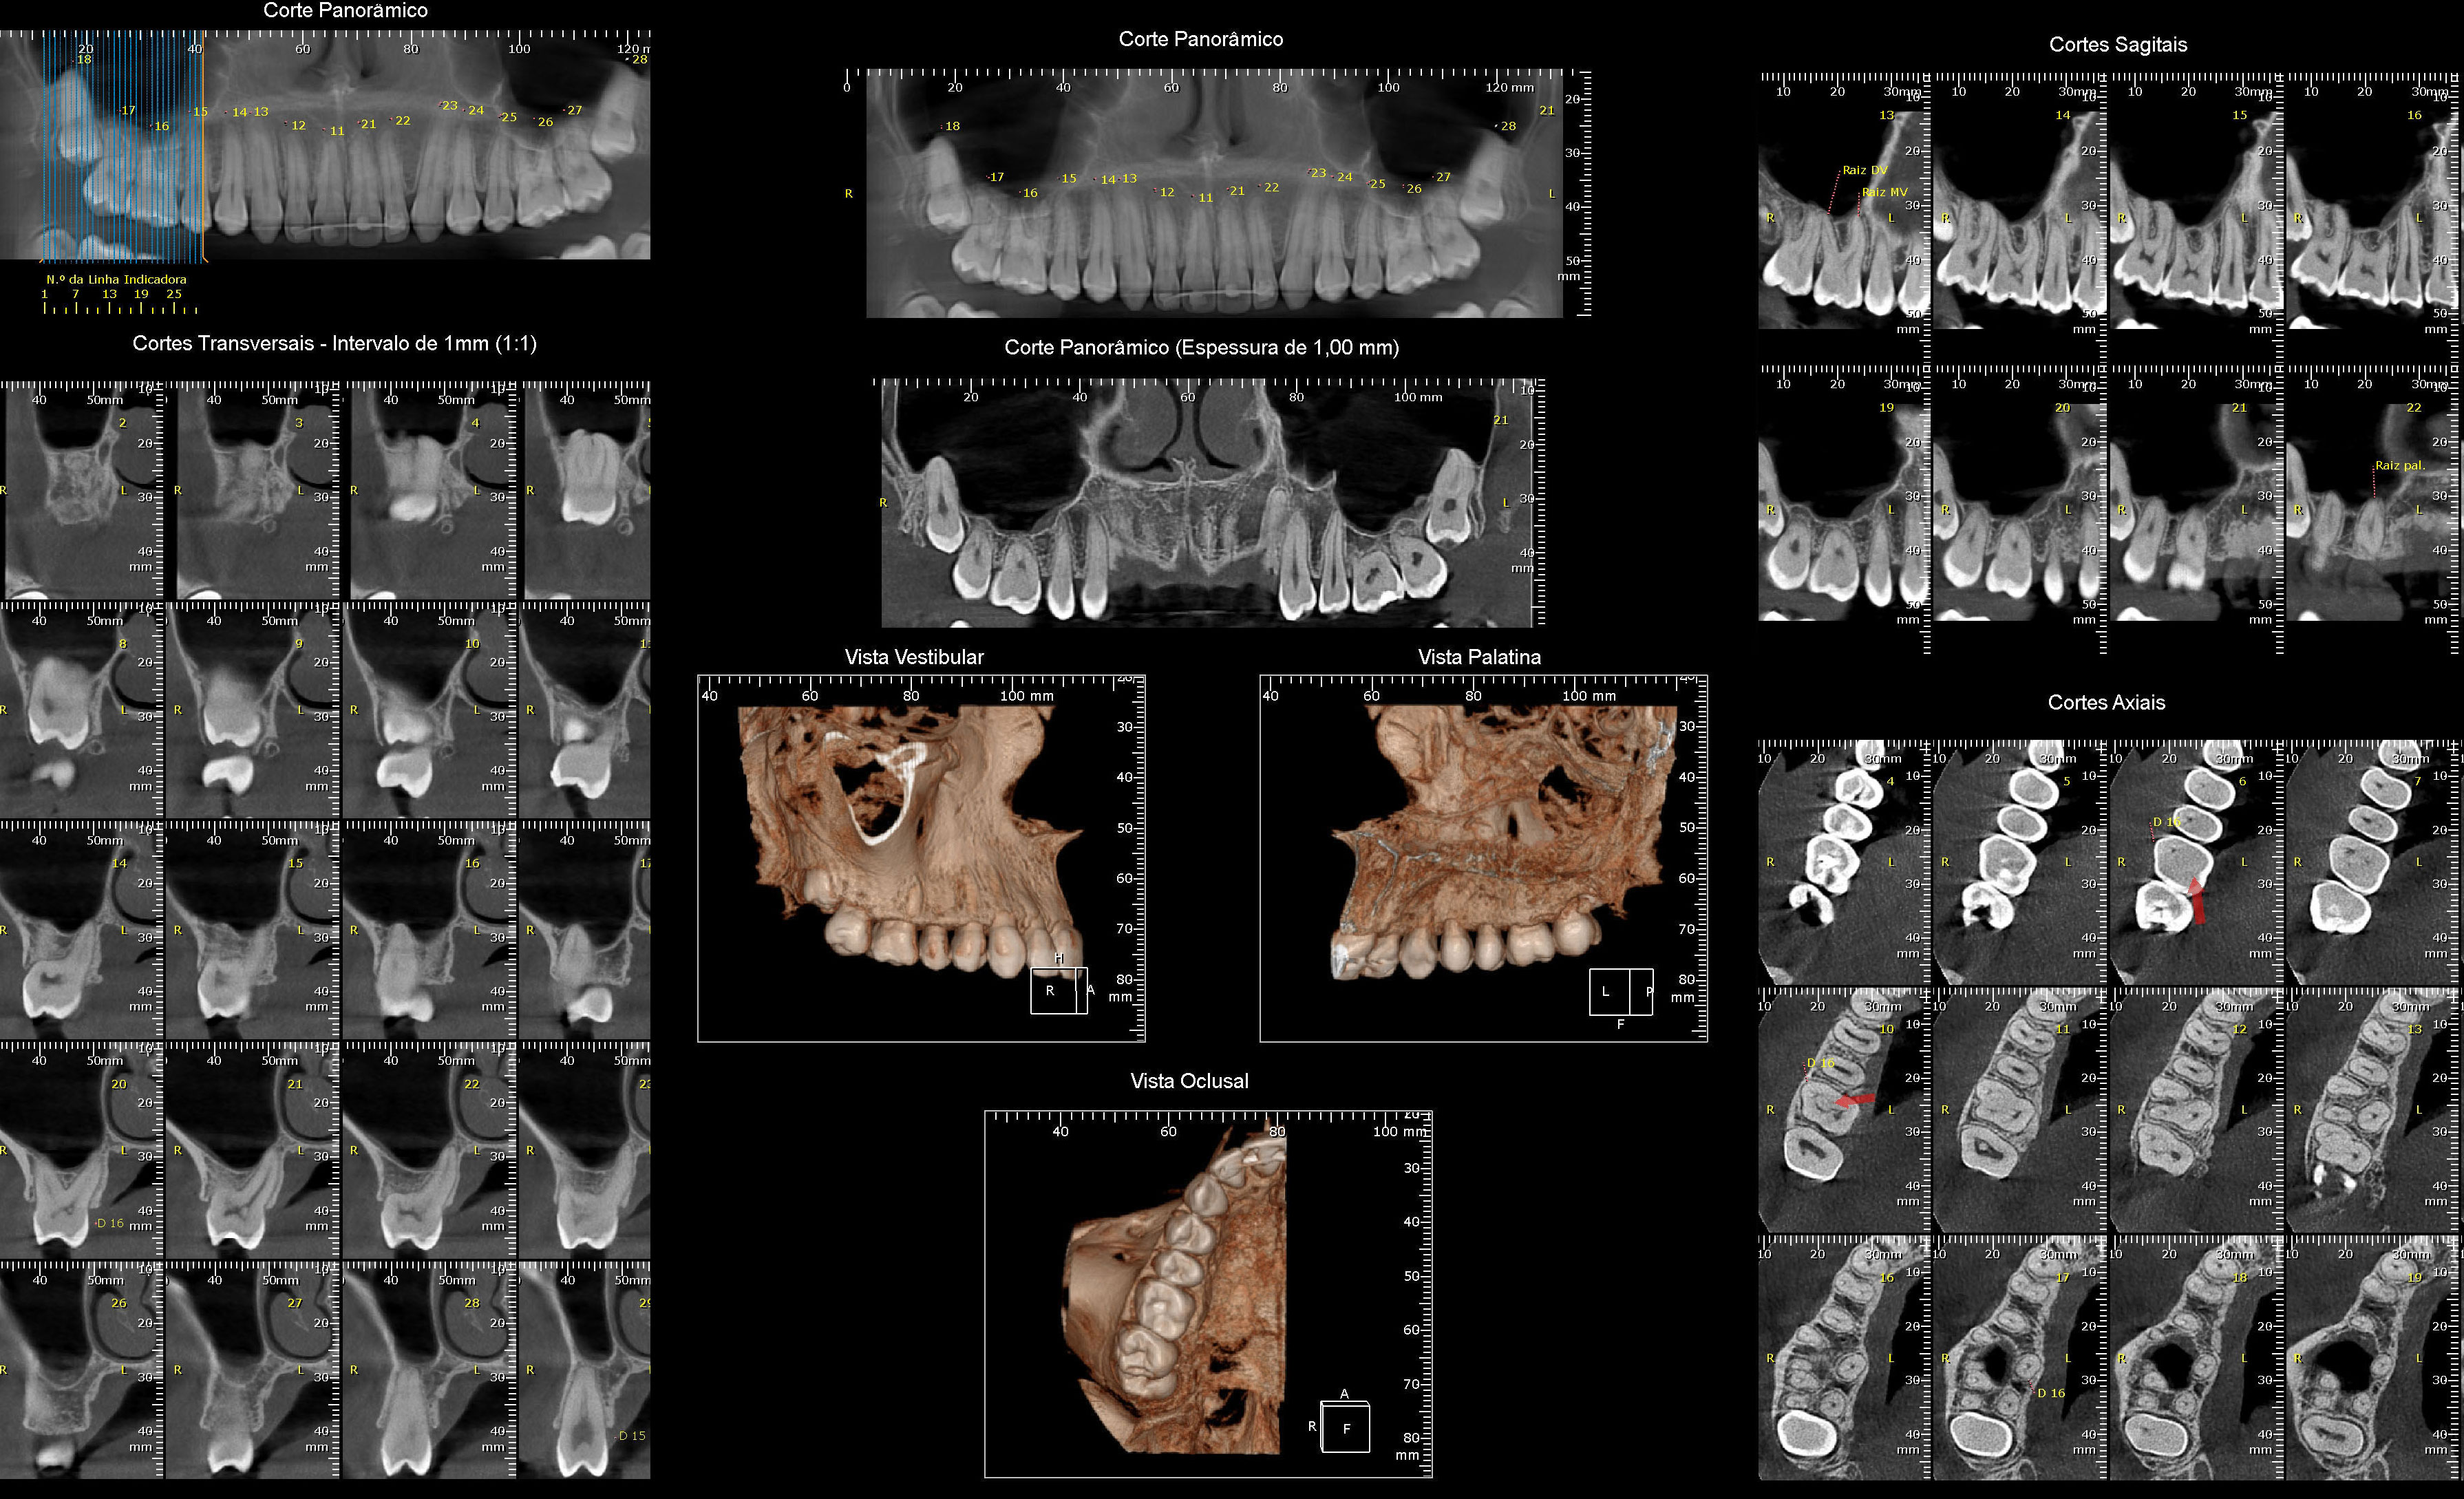

Tomografia Computadorizada

- Exame Tridimensional dos Maxilares, ATM, Seios da Face

- Tomógrafo de Altíssima Resolução Cone Beam